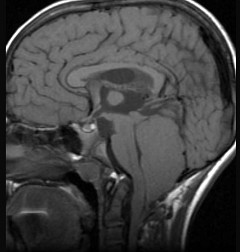

第四脑室室管膜瘤(如图所示)临床特点包括 ( ) NSJ-1192.jpg

• A.颅内高压症状较早

• B.多以头痛为首发症状

• C.伴有呕吐、头晕及强迫头位

• D.肿瘤增大累及小脑蚓部或半球时,可出现平衡障碍、步态不稳和共济失调等

• E.当肿瘤压迫脑干或脑神经时,可出现相应的脑神经障碍